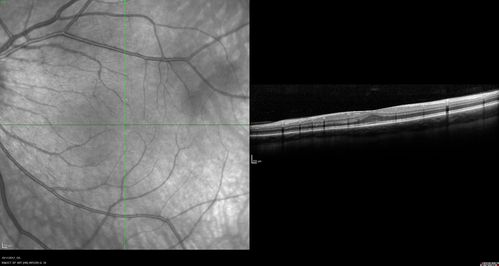

Foveal Hypoplasia in adult with ROP - good Vision

26 year old female Born at 1 lb 15 oz and had cryo for ROP at birth.

VA OD: Dcc20/25

VA OS: Dcc20/20

SD OCT shows foveal hypoplasia

The SD OCT scan shows incursion of one or more of the plexiform layers into the center of the fovea.